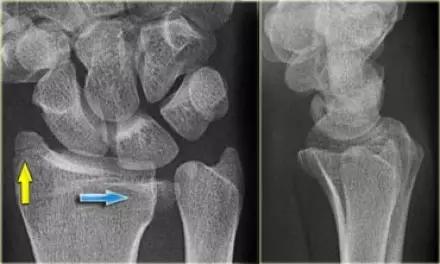

5. Chauffeur 骨折/ Hutchinson 骨折

桡骨干的斜形骨折,早期有机械性弯曲,进而通过逆性外力造成的斜形骨折。指桡骨茎突受舟骨撞击的剪切骨折形成带关节面的三角形骨折。

Essex-Lopresti 损伤。前后位(A)和侧位(B)示桡骨头关节内骨折(白色实线箭头);(C~E)伤后 1 个月复诊,患者诉腕关节疼痛,X 线(C,D)发现下尺桡关节脱位,(E)CT 进一步证实损伤的存在 (来源:Radiol Clin North Am. 2015 Jul;53(4):717-36)